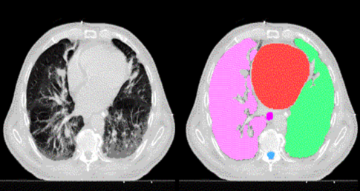

Applied Machine Learning in Medical Imaging

In collaboration with Varian Medical Systems, this project explores and applies machine learning techniques for medical image analysis. Radiotherapy planning for cancers and other disease states is a complex and time-consuming process that may be accelerated and improved by the application of machine learning techniques. The SCU team is expanding upon its previous effort, which developed automated segmentation of organs on CT images and the creation of CT and MRI image classifiers with TensorFlow tools. Students working on this project learn about medical imaging, image analysis, and the application of deep learning methods to enhance therapeutic outcomes.